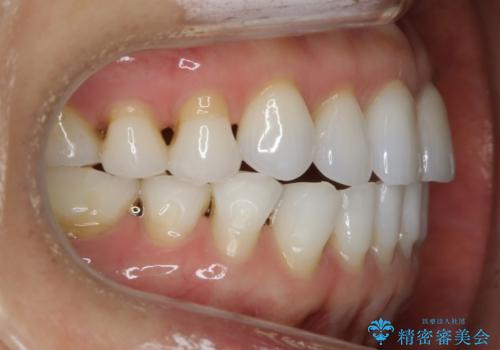

【非抜歯】マウスピースでオープンバイトを治す

- 歯ぎしりや食いしばり、噛み合わせの治療とガタつきを治したいとのことでご来院されました。

検査の結果、前歯と臼歯の高さに差があり、前歯が全く当たらない状態になっているため歯ぎしりによって奥歯が削れてしまっているという状態でした。

マウスピースの矯正装置を用い、ガタつきを治しつつ奥歯を沈めていくことで噛み合わせ全体の改善を図りました。